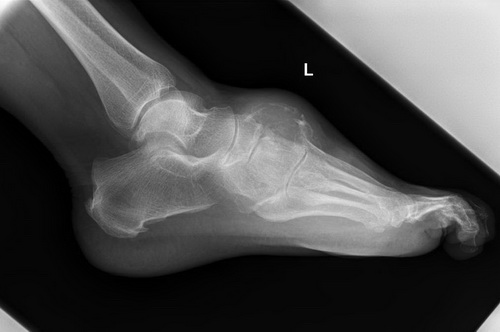

Röntgen in zwei Ebenen

Bioptisch gesichertes Chrondrosarkoms (li. Vorfuß), Indiaktion zur Amputation im Chopart-Gelenk.